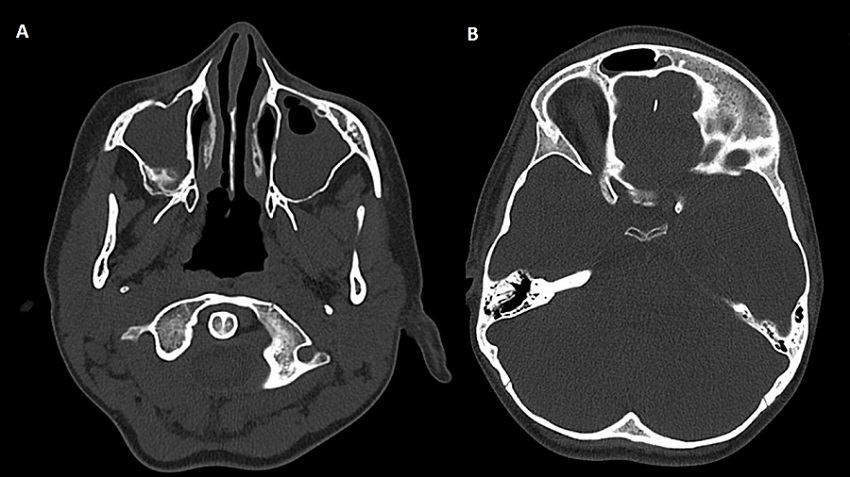

Ante sospecha de sinusitis complicada (dolor con los movimientos oculares, tumefacción de partes blandas, elevación de reactantes de fase aguda y afectación del estado general) se decide realización de tomografía computarizada craneal, hallándose una pansinusitis complicada con un absceso subperióstico intraorbitario con edema frontal circundante compatible con tumor inflamatorio de Pott (Figuras 3A y 3B).

| Figura 3. (A) Pansinusitis. Se observan senos maxilares ocupados. (B) Edema frontal (tumor inflamatorio de Pott) |